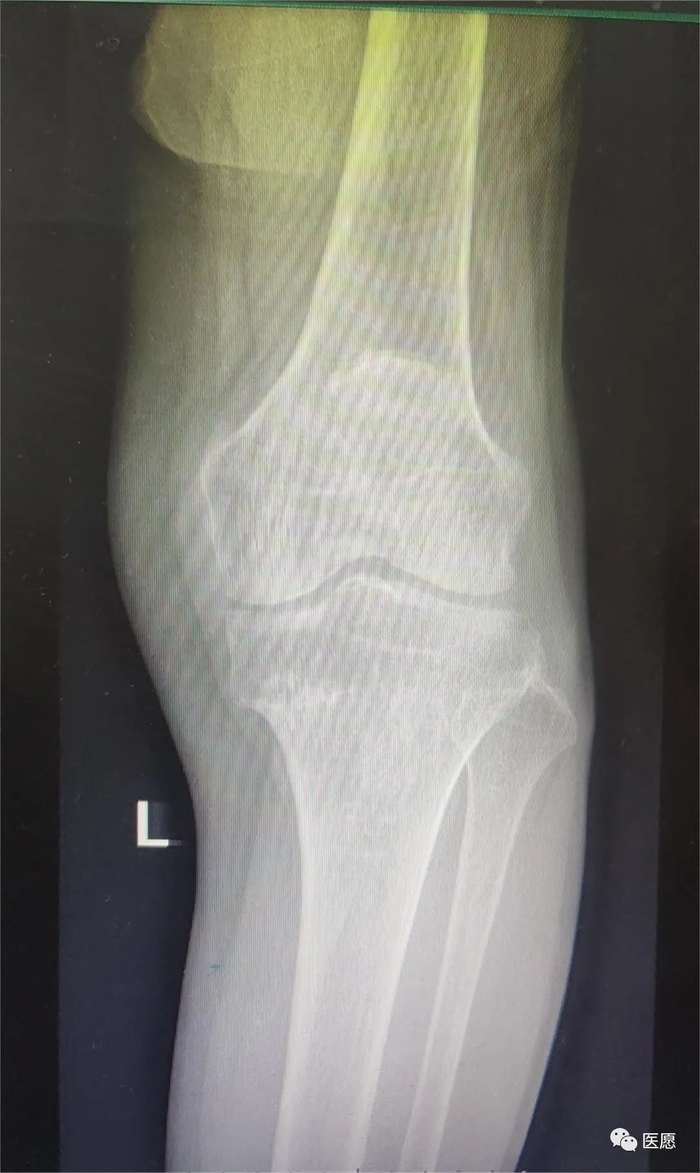

诊断】左膝骨性关节炎。

1

2